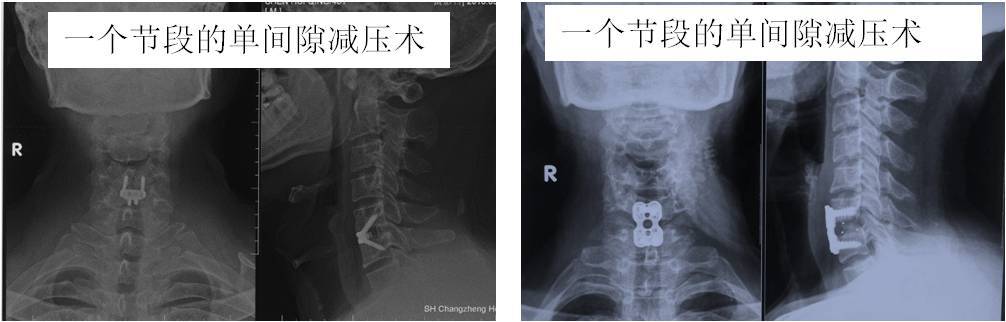

神经根型颈椎病和大多数脊髓型颈椎病可采取从脖子前面开刀(颈椎前入路),如椎间隙减压术(图6,图7),椎体次全切除术(图8)。

这种手术方式的特点是:手术微创,切口3—4公分(图9),切口美容,出血少(一般100ml),恢复快,术后1—2天可戴颈托下地行走。但对手术的技术要求较高。